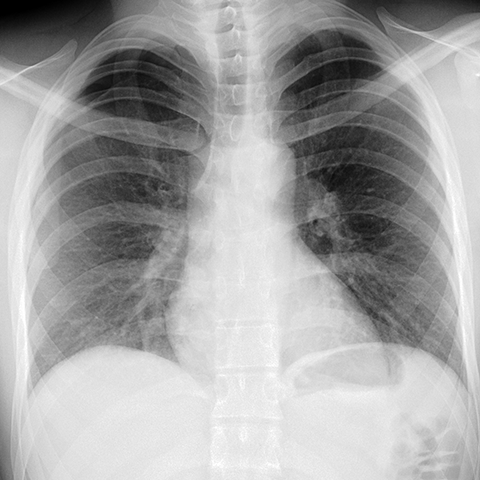

Pneumothorax [1 of 2]